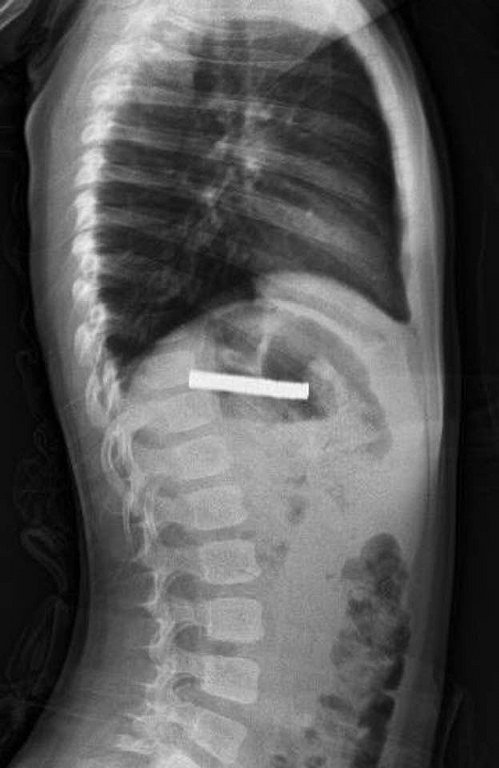

Edinilen bilgiye göre, Erzurum’da bir çocuk evde bulunan 19 tane mıknatısı yuttu. Çocuğun rahatsızlanması sonucu durumu öğrenen aile hastaneye başvurdu. Daha sonra çocuk Elazığ’a sevk edildi. Fırat Üniversitesi Çocuk Gastroenteroloji Hepatoloji ve Beslenme Bilim Dalı Başkanı Prof. Dr. Yaşar Doğan, çocuk hastanın yemek borusuna yapışmış 19 mıknatısı endoskopik yöntemle çıkardı.

Mıknatıslar uzun süre yemek borusunda takılı kaldığı için yemek borusu ve mide girişinde zedelenmeler olurken, çocuğun sağlık durumunun iyi olduğu ve taburcu edildiği öğrenildi.(İHA) -